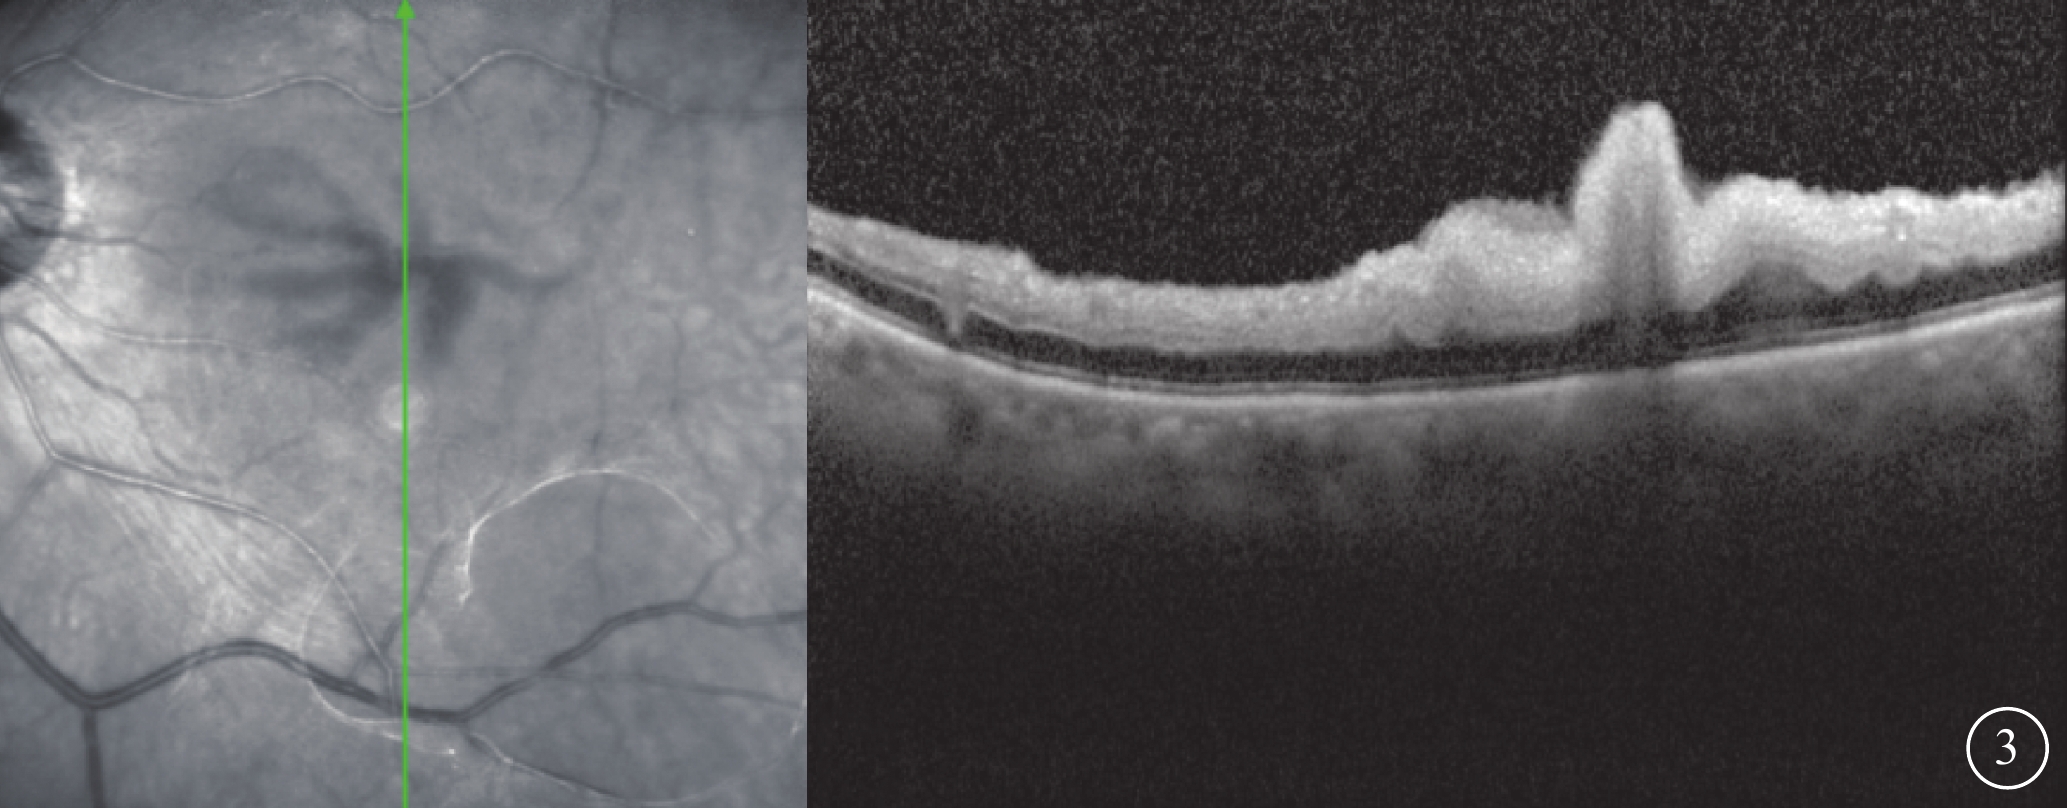

患者女,77歲。因左眼視力下降8個月加重1個月于2017年10月26日至北京大學第三醫院眼科中心就診。既往曾有晨起時一過性左眼黑矇史;否認高血壓、糖尿病等全身病史。甘油三酯輕度升高,出凝血時間正常。眼部檢查:左眼視力0.1,矯正不能提高;右眼視力0.2,矯正視力0.3。左眼眼壓(IOP)20 mmHg(1 mmHg=0.133 kPa)。晶狀體核性混濁;眼底可見黃斑前膜。右眼晶狀體混濁,其余眼前節及眼底檢查未見明顯異常。診斷:(1)左眼白內障;(2)左眼黃斑前膜。于10月28日在局部麻醉下行左眼白內障超聲乳化IOL植入、23G玻璃體切割手術(PPV)。手術參數:超聲乳化瓶高85 cm,PPV時IOP 28 mmHg。手術時間45 min,過程順利。手術后第1天,左眼視力眼前數指。角膜輕度水腫;眼底視盤邊界清楚,色澤正常,黃斑區輕度水腫。IOP 37 mmHg,給予降眼壓藥物控制。手術后第2天,患者自述晨起時左眼黑矇,檢查左眼視力上方眼前手動。眼底視盤邊界清楚,顏色淡;后極部視網膜灰白水腫,無櫻桃紅斑(圖1A),視網膜動脈內血流中斷;視盤鼻側見羽毛狀灰白水腫楔狀區域(圖1B),與視網膜血管分布不一致。IOP 18 mmHg。FFA檢查,視盤和脈絡膜充盈遲緩,視網膜中央動脈14″ 73開始充盈,可見動脈前鋒,21″17靜脈尚未完全充盈;25″92視盤鼻側開始顯現由邊界清楚羽毛狀強熒光拼成的楔形區域,隨時間延長熒光增強,但始終邊界清楚(圖2A)。次日ICGA檢查,脈絡膜充盈遲緩,至10′42″20時視盤鼻側開始出現脈絡膜強熒光區,與FFA所見形態部位一致(圖2B)。OCT檢查,視網膜內層彌漫強反射,層次不清,黃斑中心凹處呈皺褶狀隆起(圖3),鼻側病灶區脈絡膜層面異常反射不顯著。頸動脈彩色多普勒血流顯像(CDFI)檢查,雙側頸動脈硬化斑塊形成。心臟CDFI檢查,左室泵功能正常,舒張功能減低;主動脈瓣輕度關閉不全。神經內科初步診斷:頸內動脈系統短暫性腦缺血發作。頭頸部CT血管造影(CTA)檢查,雙側頸內動脈起始部血管壁混雜斑塊形成,管腔變窄。頭顱CT檢查,多發腔隙性腦梗死,軟化灶。腦白質疏松,腦萎縮。未行頭頸部數字減影血管造影。24 h橈動脈動態血壓監測結果:白天平均血壓121/60 mmHg,脈壓差60.7 mmHg;夜間平均血壓110/51 mmHg,脈壓差59.7 mmHg。最終臨床診斷:(1)左眼脈絡膜三角綜合征;(2)左眼視網膜中央動脈阻塞(CRAO);(3)左眼內低灌注。

左眼手術后第2天OCT像。左圖為掃描部位和方向,右圖為檢查結果。視網膜內層彌漫強反射,層次不清晰,黃斑中心凹處呈皺褶狀隆起

左眼手術后第2天OCT像。左圖為掃描部位和方向,右圖為檢查結果。視網膜內層彌漫強反射,層次不清晰,黃斑中心凹處呈皺褶狀隆起

圖3

左眼手術后第2天OCT像。左圖為掃描部位和方向,右圖為檢查結果。視網膜內層彌漫強反射,層次不清晰,黃斑中心凹處呈皺褶狀隆起

圖3

左眼手術后第2天OCT像。左圖為掃描部位和方向,右圖為檢查結果。視網膜內層彌漫強反射,層次不清晰,黃斑中心凹處呈皺褶狀隆起